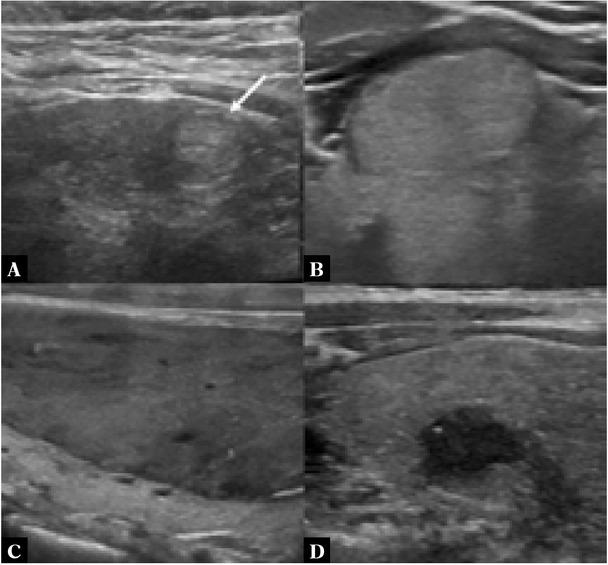

The background thyroid parenchyma and adjacent neck musculature are used as the reference for determining the echogenicity of thyroid nodules. Compared to the thyroid parenchyma, hyperechoic nodules have higher echogenicity, isoechoic nodules have similar echogenicity, while hypoechoic nodules have lower echogenicity (Fig. 2) (3). Conversely, very hypoechoic nodules have lower echogenicity than the neck musculature(3). To improve the accuracy and consistency of interpretation, these findings should be evaluated on several tissue planes on the still and cine images.

Fig. 2

Greyscale sonographic images of: A. a hyperechoic nodule (white arrow) with higher echogenicity compared to the adjacent thyroid parenchyma; B. an isoechoic nodule with similar echogenicity to the adjacent thyroid parenchyma; C. a hypoechoic nodule with lower echogenicity compared to the adjacent thyroid parenchyma; and D. a very hypoechoic nodule with lower echogenicity compared to the neck musculature